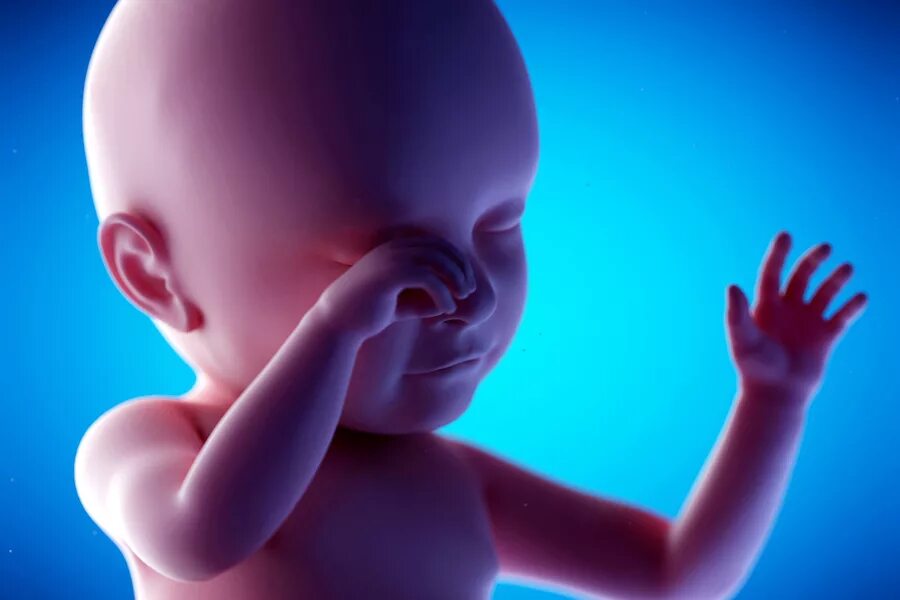

Ребенок в животе 22 недели